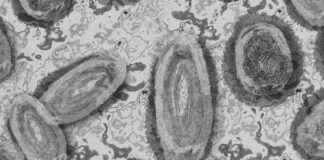

OMS evalúa si viruela de mono representa una ‘urgencia sanitaria’

Tedros Adhanom, director general de la OMS, convocó a diferentes organismos internacionales para evaluar el comportamiento de la viruela del mono

OMS reporta 780 casos de viruela de mono

De acuerdo con el monitoreo de la OMS, hasta el 5 de junio de 2022 se han reportado un total de 780 casos de viruela del mono, la mayoría en Europa

OMS reporta 92 casos de viruela de mono en 12 países

La Organización Mundial de la Salud (OMS) informó que hay 92 casos activos de viruela del mono en 12 países

EU y Canadá: primeros casos de Viruela del Mono en América

La Viruela del Mono ha llegado a América, esto luego de que Estados Unidos confirmó este 18 de mayo su primer caso, mientras que Canadá informó que se investigarán 13 casos sospechosos.